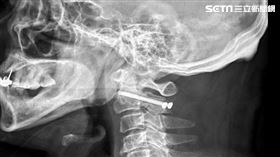

男騎機車出車禍 竟絞刑式骨折險癱瘓

台中66歲陳先生因騎機車出車禍,被送往醫院急救,到院...